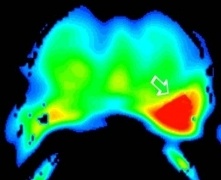

Figure 2 is biopsy proven prostate adenocarcinoma in a 62-year-old man with a Gleason grade of 6 (3+3). This example shows how functional imaging can help identify the tumor.

Figure 2c: DCE images demonstrate a focal area of abnormal enhancement in the left mid gland (solid white arrow) corresponding to the region of tumor confirmed at prostatectomy.